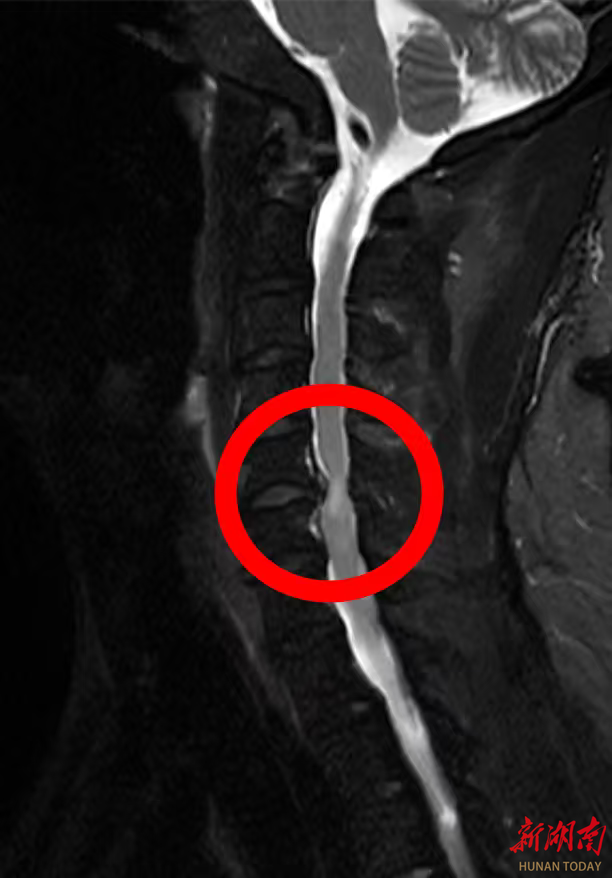

李先生谈及患病经历时满是感慨:“自从得了颈椎病,实在是太痛苦了,颈肩部疼痛,双上肢持续疼痛麻木,让人难以忍受,近期夜间更是因疼痛辗转难眠。”为缓解病痛,他尝试过口服中药、西药、理疗等多种保守治疗,但症状反复发作且逐渐加重,多次求医问诊效果均不理想。经该院脊柱外科团队详细检查,李先生被确诊为“颈椎间盘突出(C5-6节段)伴脊髓压迫”。医生明确告知,若不及时手术,可能导致神经不可逆损伤,甚至出现瘫痪症状,需尽快干预治疗。

“传统颈椎融合术虽然能解除压迫,但失去一个椎间盘的活动单元后颈椎活动度会有减少,而李先生仅45岁,对颈椎活动需求比较高。”经该院脊柱外科团队反复研讨,结合李先生的年龄和对颈部活动功能的需求,最终决定采用人工颈椎间盘置换术这一先进术式。该技术作为目前国际脊柱外科的主流前沿技术,打破了传统手术“融合固定”的局限,具有技术更先进、创伤更微小、恢复更快捷三大核心优势。仿生假体模拟天然椎间盘功能,保留颈椎活动度,降低远期并发症风险;小切口、少出血,减少组织损伤和术后疼痛;术后无需长期制动,患者能快速回归正常工作生活。通过植入仿生人工椎间盘,既能彻底解除神经压迫,又能完整保留颈椎的屈伸、旋转功能,从根本上避免了传统手术带来的颈部僵硬问题。